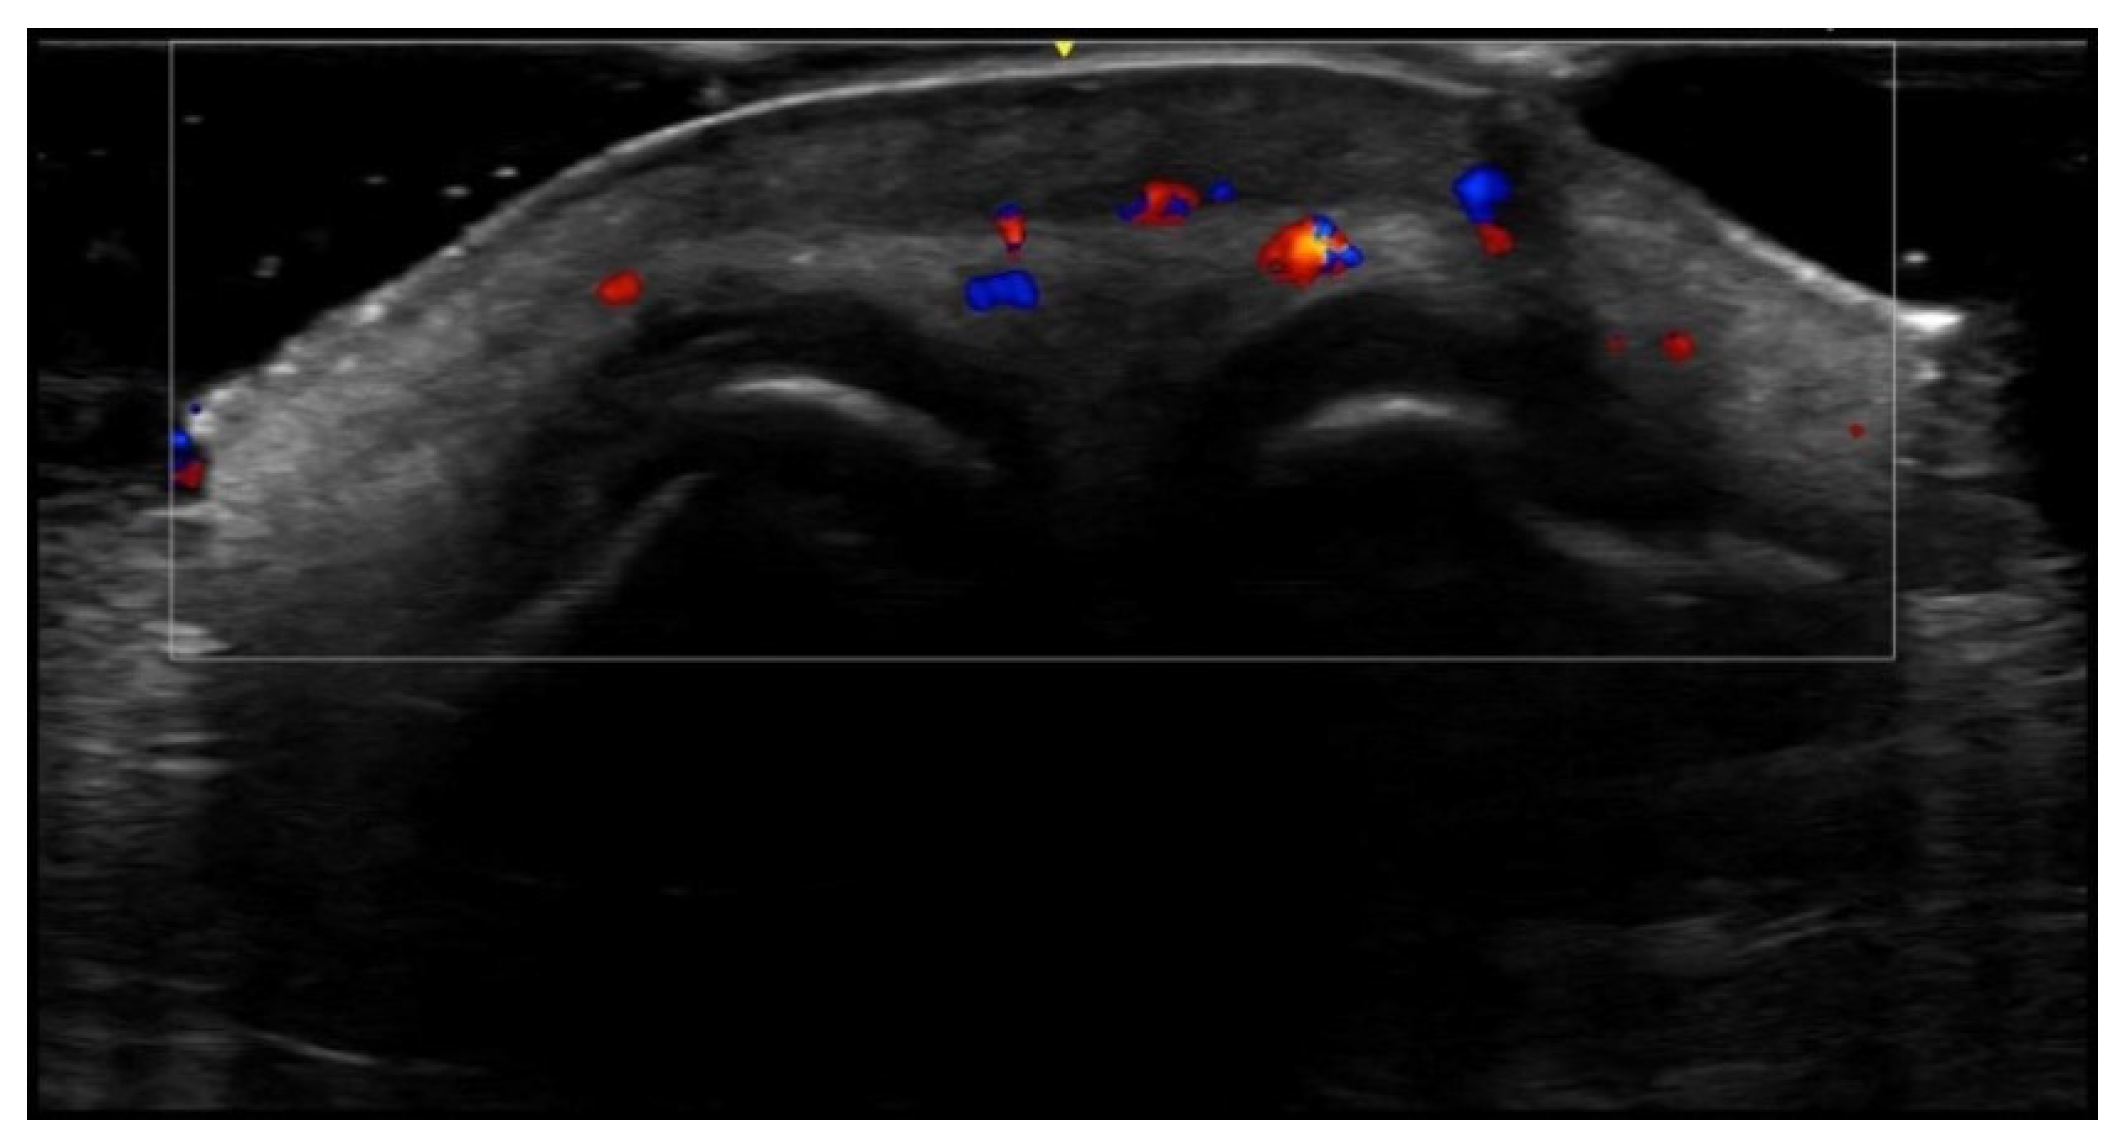

- Velthuis, P.J.; Jansen, O.; Schelke, L.W.; Moon, H.J.; Kadouch, J.; Ascher, B.; Cotofana, S. A Guide to Doppler Ultrasound Analysis of the Face in Cosmetic Medicine. Part 1: Standard Positions. Aesthetic Surg. J. 2021, 41, NP1621–NP1632. [Google Scholar] [CrossRef]

- Vasconcelos-Berg, R.; Izidoro, J.F.; Wenz, F.; Müller, A.; Navarini, A.A.; Sigrist, R.M.S. Doppler Ultrasound-Guided Filler Injections: Useful Tips to Integrate Ultrasound in Daily Practice. Aesthetic Surg. J. 2023, 43, 773–783. [Google Scholar] [CrossRef]